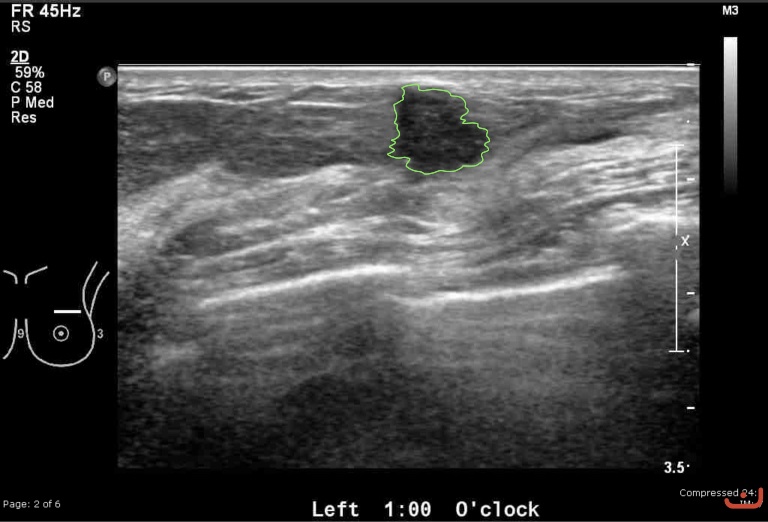

Case 27-G1

Malignant solid mass

Friday, 22 May 2015

169.76 KB (768 x 522 px)